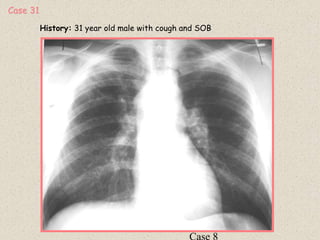

History: 31 year old male with cough and SOB

Case 31

Diagnosis : Stage 2 sarcoidosis

Radiographic findings:

1: Bilateral hilar lymphadenopathy

2: Bilateral upper lobe interstitial pattern

Close up RUL